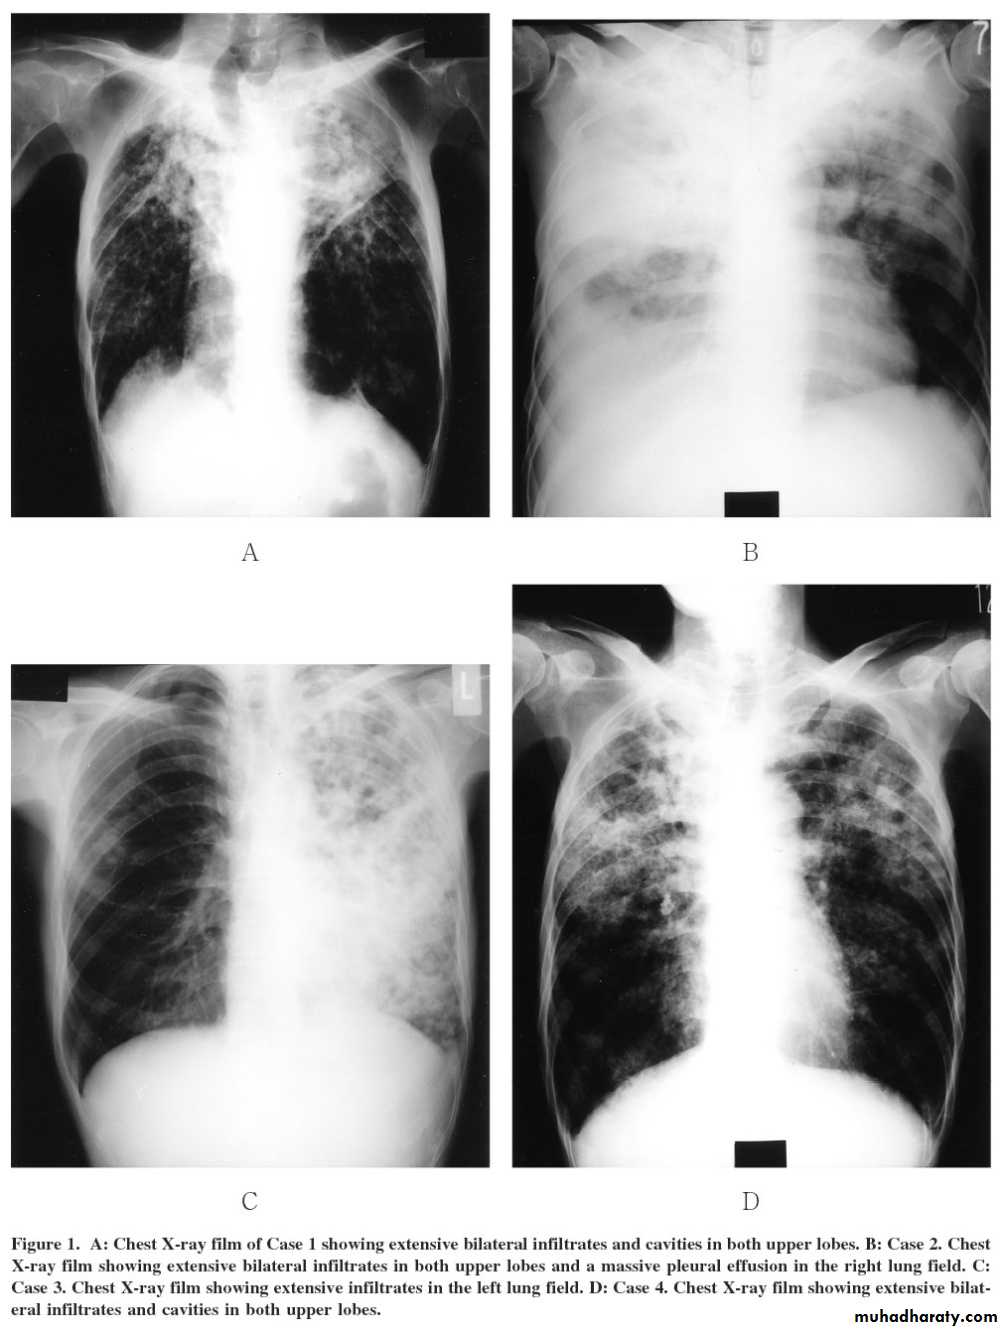

Post primary tb

TB lung